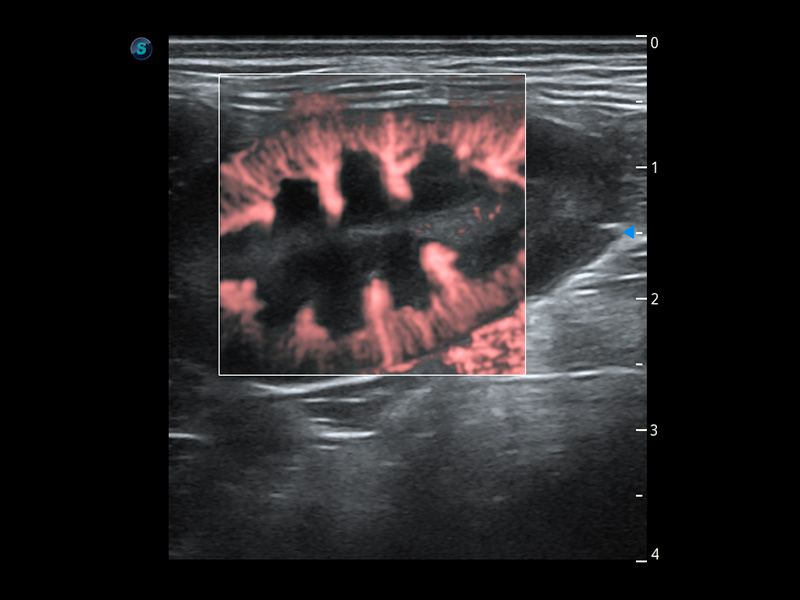

ProPet 60 作為一款高端臺式動物超聲設(shè)備,為動物醫(yī)生的日常診斷提供了一系列貼合動物臨床需求、解決臨床實(shí)際問題的高級成像功能。憑借全系列高清探頭,滿足醫(yī)生對腹部、心臟、生殖、淺表、肌骨等成像的所有需求,切實(shí)幫助您提升檢查效率,提高診斷信心。